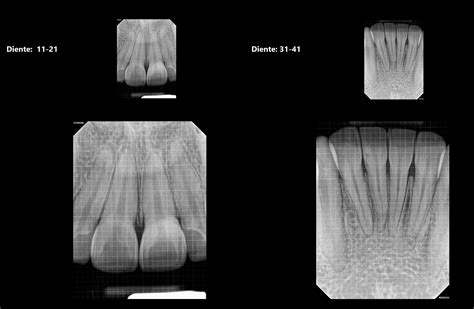

- Radiografías periapicales: Permiten observar el diente completo, con las raíces y el hueso.

- Radiografías interproximales o de aleta de mordida (bitewing): Permiten observar las coronas de los dientes superiores e inferiores en una misma imagen, enfocándose en las áreas de contacto entre dientes.

¿Qué aspecto tiene una caries en una radiografía?

La desmineralización y destrucción de las capas del diente se observa como una imagen radiolúcida (zona negra alrededor/dentro del diente). En la imagen que señala la flecha vemos una imagen radiolúcida (oscura) que indica la falta de material dental, la presencia de una zona “hueca”. Caries.